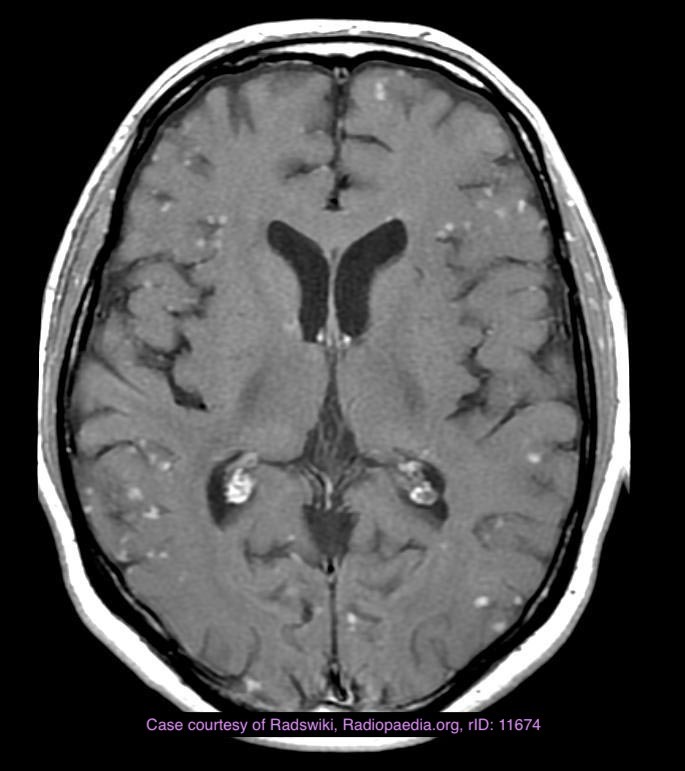

Immunocomprimised : Fulminant CNS disease. Basal ganglia, Corticomedullary junction. solitary or multiple ring enhancing lesions with marked surrounding edema. Eccentric target appearance. After treatment lesions may calcify or haemorrage.

CNS capillary telangiectasiae(s) are small, asymptomatic low flow vascular lesions of the brain.

As these lesions are asymptomatic, diagnosis usually matches the age of first imaging with MRI, and as such are most frequently found in middle-aged and elderly adults. Their incidence varies according to the series. They can account for up to ~20% of all intracerebral vascular malformations on autopsy studies 2 and are considered the second most common vascular anomaly after venous angiomas (developmental venous anomaly) on imaging 5.

The vast majority of capillary telangiectasias are completely asymptomatic and discovered incidentally on MRI when the brain is imaged for other reasons.

Occasionally there may be associated intracerebral haemorrhage, although a direct causative relationship has not been established beyond a doubt. This may be more common with cases of mixed histology.

They are comprised of dilated capillaries and are interspersed with normal brain parenchyma with a thin endothelial lining but no vascular smooth muscle of elastic fibre lining. This is in contrast to cavernous malformations (CM) which have no normal brain within their confines. Histology can be mixed with a component of CM.

most occur in the pons, cerebellum and spinal cord

Osler-Weber-Rendu syndrome

Capillary telangiectasias are mostly located in the brainstem (especially the pons). They are more often solitary, but sometimes can be multiple. They have only become widely recognised in the radiology community following the introduction of MRI, as they are usually not seen on CT and DSA 2-5.

They appear as subtle lesions with no mass effect.

T1: typically iso to low signal compared with brain parenchyma

T2: normal or slightly increased signal intensity

FLAIR: normal or slightly increased signal intensity

T2*: low signal intensity

thought to be due to deoxyhaemoglobin from sluggish flow, not haemorrhage 2

T1 C+:

may demonstrate stippled enhancement

if large, can show branching/linear draining veins